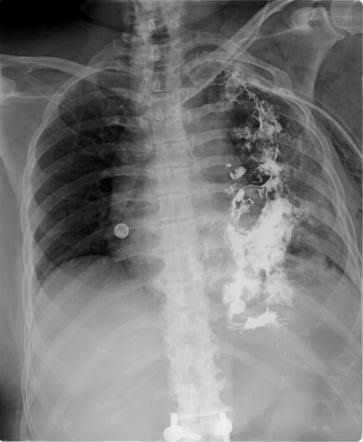

Boerhaave syndrome is one of the most lethal gastrointestinal tract disorders, with mortality rates up to 40%. Symptoms may vary, and diagnosis can be challenging. Also, several factors, including difficulty assessing the esophagus and the unusual blood supply of the organ, contribute to the condition’s high morbidity. Without treatment, the survival of Boerhaave’s syndrome can be days. Management relies on rapid recognition and intervention as a lack of therapeutic interventions can be fatal. Boerhaave syndrome is due to the rupture of the esophagus due to forceful emesis. The disorder may present with vague symptoms, or one may note the classic Mackler triad of vomiting, chest pain, and subcutaneous emphysema. The earlier the diagnosis made, the better the outcomes.